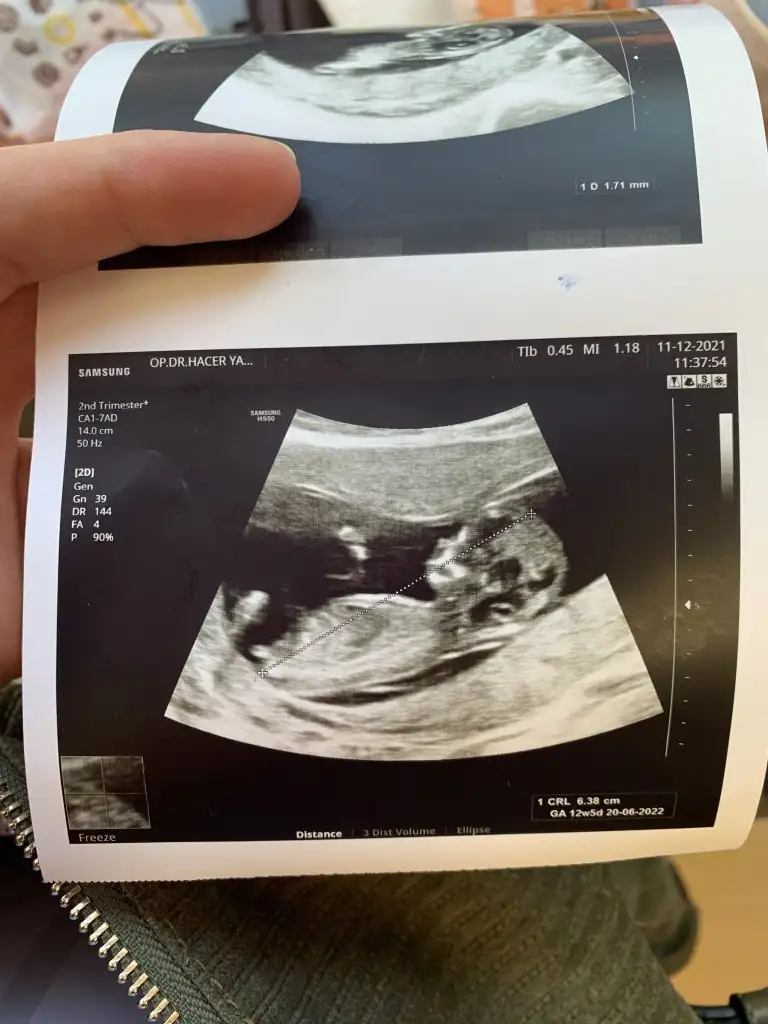

Kızlar çıktım şimdi, 13+0, haftasıyla uyumlu çok şükür.

2’li test istemedik, tekrar ense kalınlığına baktı, 1.2 gayet iyi dedi.

Veeee Ramzi amcam yanılmadı, bir erkek daha geliyo inşallah.

Kızlar bende şimdi çıktım herşey yolunda çok şükür ense kalınlığıda iyi ikili test biz istemedik cinsiyet kıza benziyor dedi ama en iyi bı ay sonra beli olur geçen hafta da devlet hastanesindeki doktor erkeğe benziyor demişti kafam iyice karıştı hayırlısı olsun inşallah çok güzel oynuyordu 12+2 haftalık miş